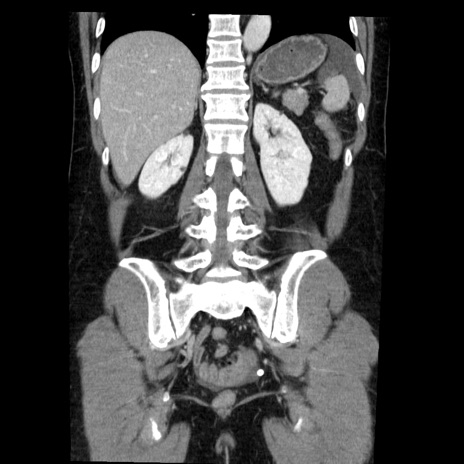

症例6(冠状断像)

【症例】50歳代女性

【主訴】下腹部痛

【既往歴】卵巣癌術後(8年前に当院で卵巣摘出)

【身体所見】 意識清明、腹部:平坦、腸蠕動音→、やや硬、下腹部自発痛・圧痛あり、反跳痛あり、筋性防御なし。

【データ】WBC 16000、CRP 0.01